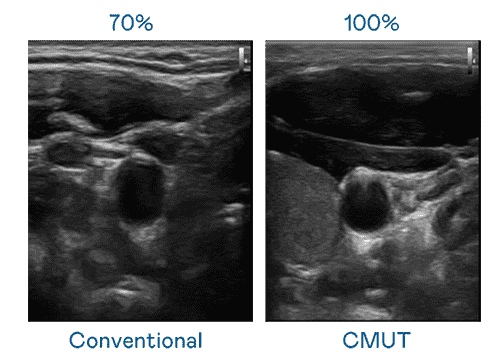

CMUT 技术是一种用电容式微机电元件来产生超音波讯号的技术。。与传统 PZT 压电式技术相比,,,CMUT 频宽增加 30%,,,更宽频的超音波讯号让影像解析度大幅提升,,,,是实现高影像品质医疗超音波扫描、、、促进精准医疗发展的关键技术。。。

大频宽带来超清晰影像

超音波影像的解析度高低,,,,首先取决于探头能发出的讯号频宽。。优游UB8 CMUT 可提供高清晰的超音波讯号,,,,提供高频宽、、、高灵敏度、、、、影像纹理细节更高的超音波影像,,,协助医护人员缩短影像判读时间及利用精准的医疗影像进行诊断。。